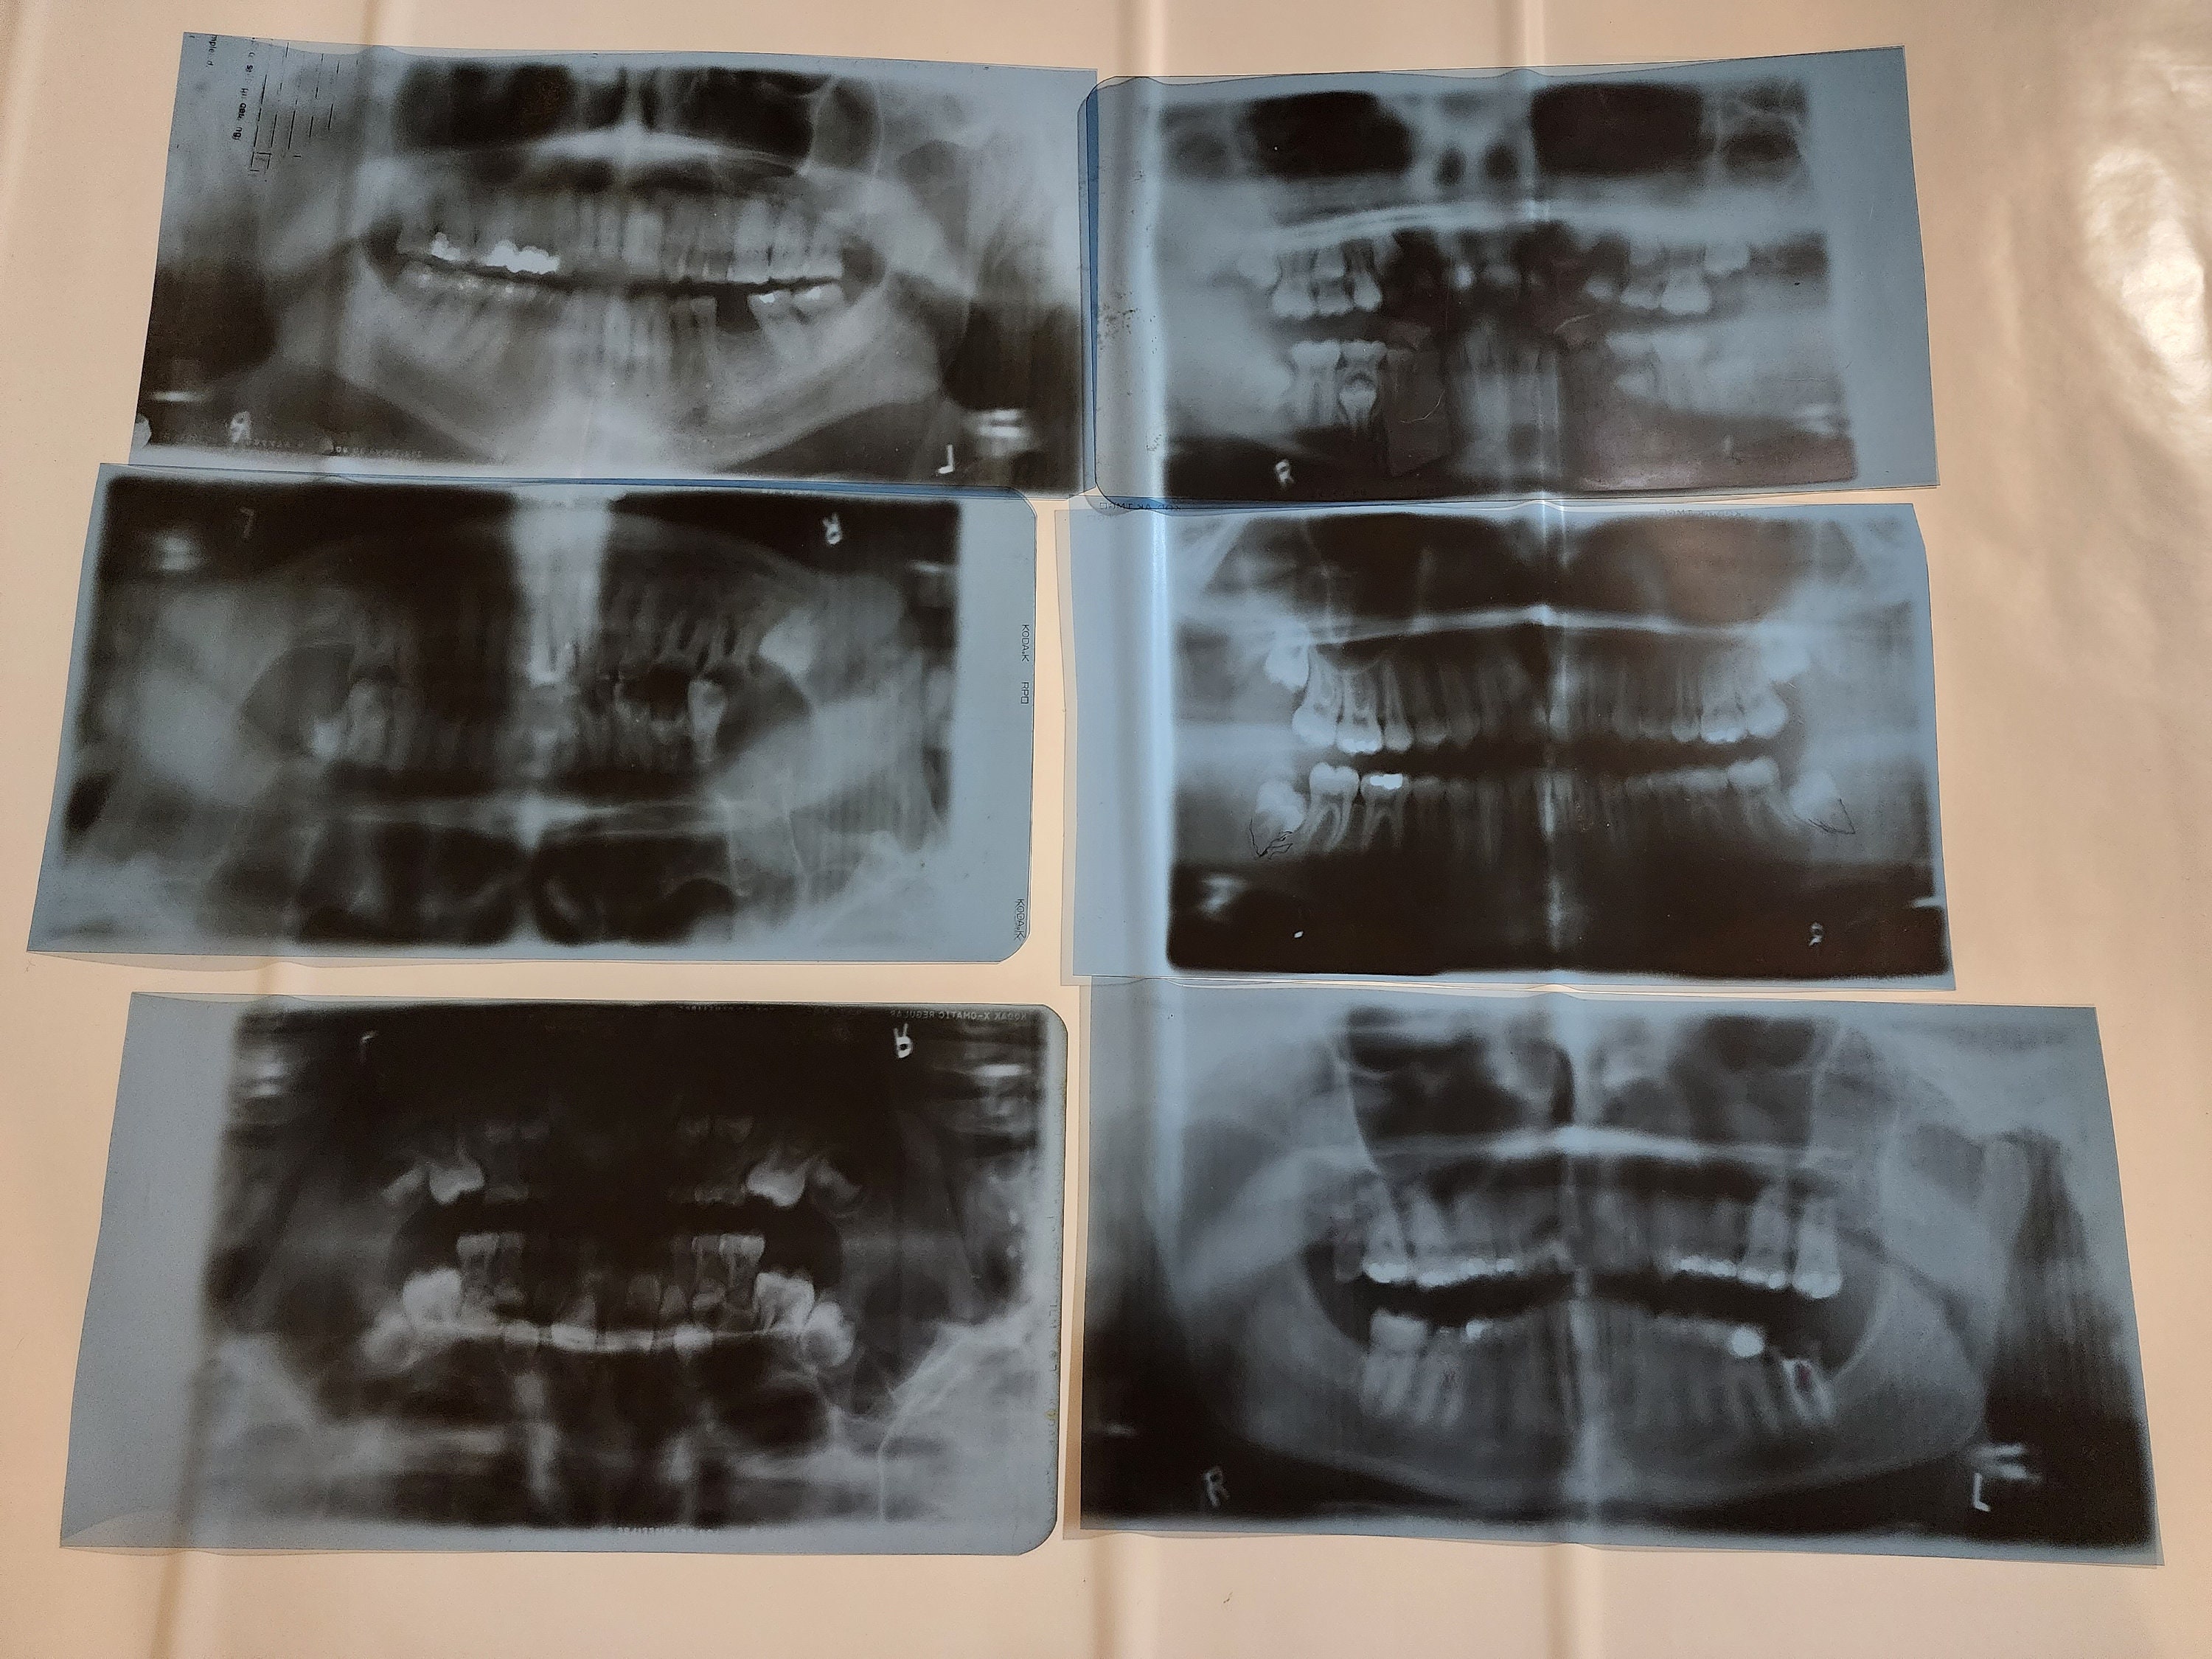

Xrays Hornell, NY Gentle Dentist

Full Mouth XRays ddi Imaging Centers Dental Code For Full Mouth X Rays What follows are typical guidelines for many u.s. It is used mainly to focus on a single tooth representing a specific area or. This is the dental code used for a radiographic survey of the whole mouth, usually. The current full entry first published in cdt 2023 is:. Cdt code d0210’s nomenclature and descriptor were revised, effective january 1, 2023.. Dental Code For Full Mouth X Rays.

Full Mouth XRay (OPG) Shanti Dentals Dental Code For Full Mouth X Rays This procedure is meticulously performed to. Cdt code d0210’s nomenclature and descriptor were revised, effective january 1, 2023. It is the intraoral periapical first radiographic image. This is the dental code used for a radiographic survey of the whole mouth, usually. The current full entry first published in cdt 2023 is:. It is used mainly to focus on a single. Dental Code For Full Mouth X Rays.

Panoramic Radiograph Skull Full Mouth Xray Human Disease Oral Surgery Dental Code For Full Mouth X Rays The current full entry first published in cdt 2023 is:. It is used mainly to focus on a single tooth representing a specific area or. This is the dental code used for a radiographic survey of the whole mouth, usually. What follows are typical guidelines for many u.s. This procedure is meticulously performed to. It is the intraoral periapical first. Dental Code For Full Mouth X Rays.